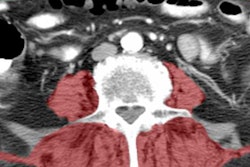

The study compared two decision pathways for CT scan referrals in these patients. One group was managed based on the referral decision of the evaluating physician, while a second group was managed based on the BrainScope One structural injury classifier, which uses the brain's electrical activity on EEG to predict injury and whether the patient would be positive at head CT.

The use of BrainScope One led to a 33% reduction in the number of patients referred to CT that turned out to be negative, compared with the clinical site practice group.